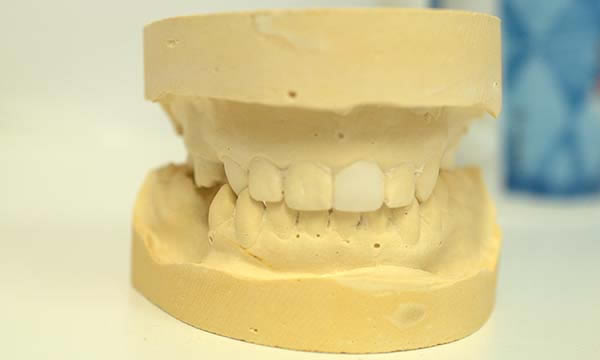

A failed apicectomy in the UL1 was diagnosed after a history of labial draining discharge and mobility. The patient was referred to us for treatment and a diagnostic wax up was used to discuss the proposed finished crown, estimated gingival margin position and crown height with the patient.

A tooth bourn position guide allowed for predictable implant placement within the aesthetic zone. Collaboration with with Smile Dental Laboratory and clinical pictures helped to produce a great shade match and natural looking result.